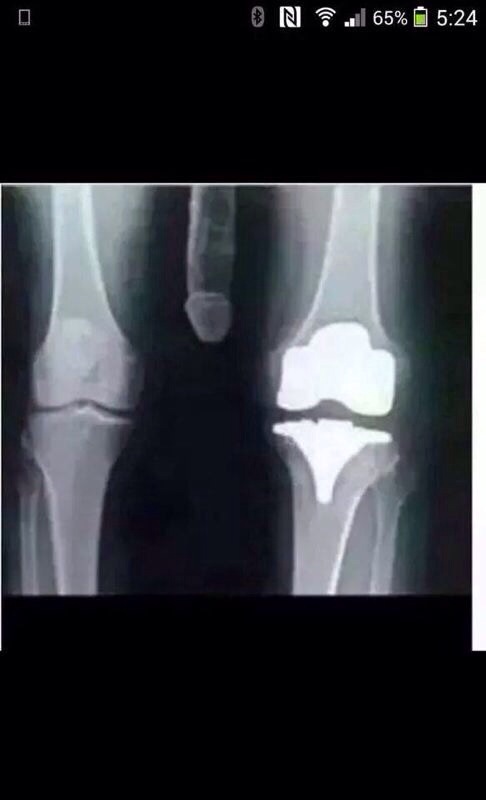

15. having a bit of trouble with my knees, joint creaking a bit, so i went for had an X-ray today.

Kneephoto_zps1fec55d7.jpg